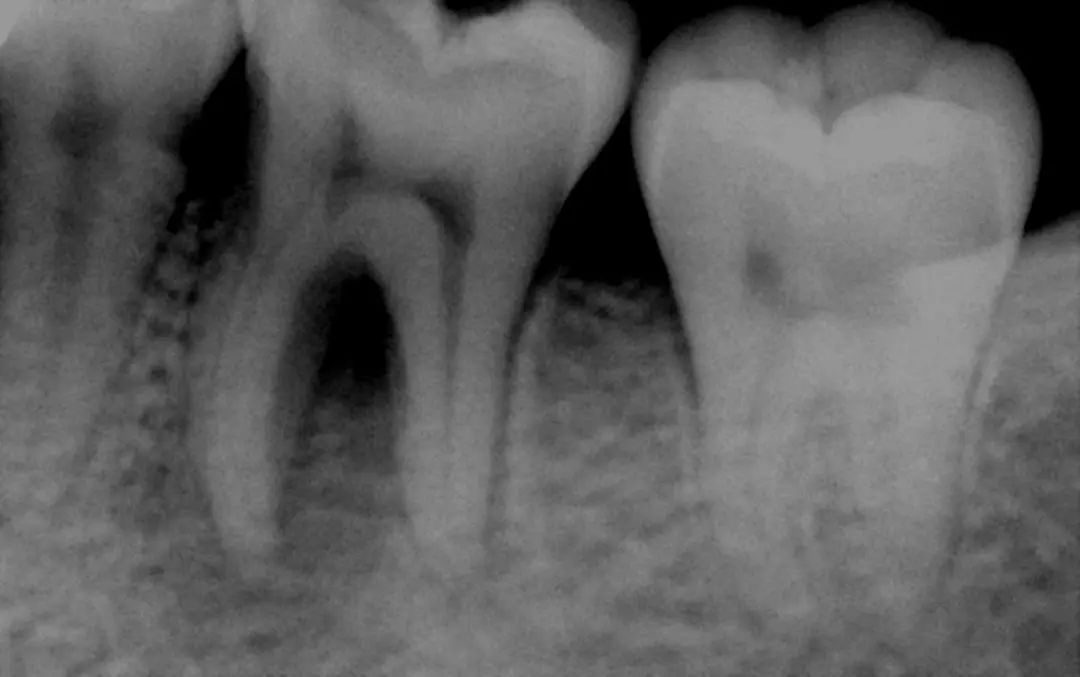

换牙期的儿童牙齿和成年人的恒牙图:换牙时,乳牙的牙根会主动溶解,恒牙则会从下方长出,另外增加的侧门齿和臼齿会从颌骨中萌发

所以,最好先去医院检查一下,医生一般会通过做X光片来检查恒牙是否埋伏在牙床里,以及是否存在发育上的问题。